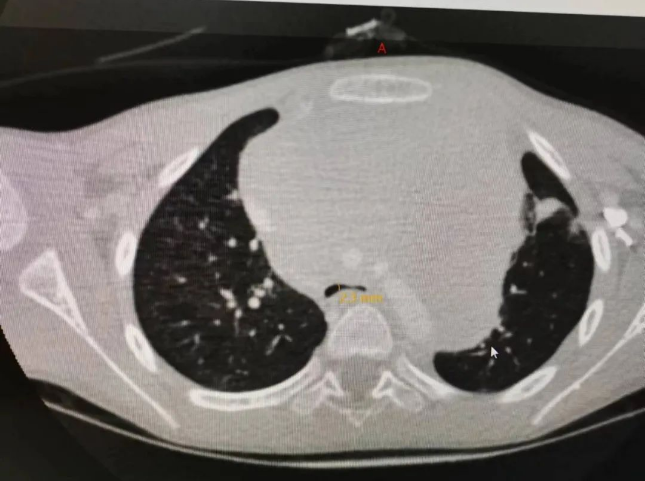

CT影像上,一个可怕的结果显露出来。恩恩的前纵隔有个巨大的实性占位,112mm×80mm×107mm,瘤体上极到了甲状腺下极,下极到心脏下缘,包绕主气道很长一段直到气管分叉处,而且瘤体压迫主气道,前后径最窄处仅有2mm,左主支气管基本被压扁,瘤体包绕主动脉弓、头臂干、左侧颈总动脉、左锁骨下动脉,推挤肺动脉、上腔静脉。